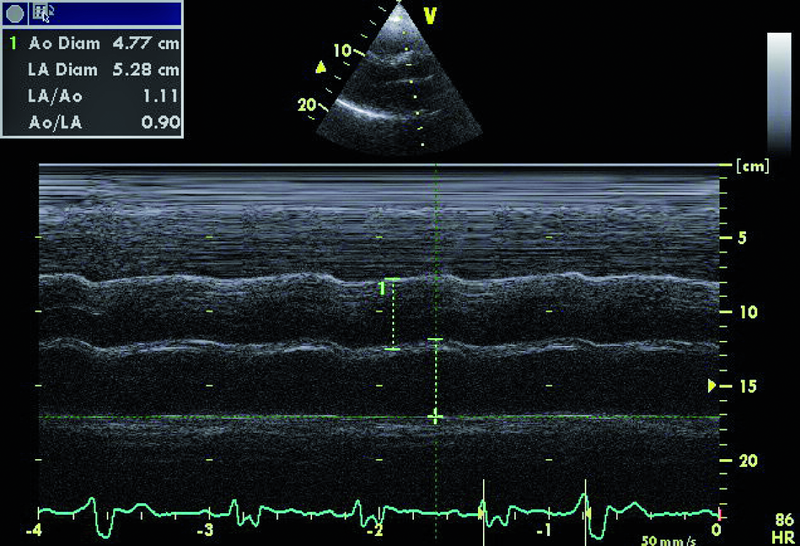

1. Poszerzenie opuszki aorty (ryc. 1, 2).

2. Powiększenie jamy lewego przedsionka (ryc. 1).

9. Komorowe zaburzenia rytmu (ryc. 1, 6).